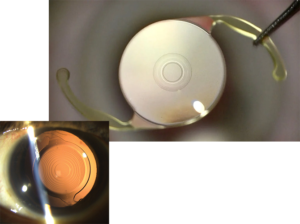

RLE, also known as lens replacement surgery or clear lens extraction, is a procedure where the eye’s natural lens is removed and replaced with an artificial Intraocular Lens (IOL). It is used to correct refractive errors such as near-sightedness (myopia), farsightedness (hyperopia), and astigmatism.

There are a number of different types of IOLs that can be used for RLE depending on your visual goals and unique eye configuration. Options include monofocal lenses (which correct for distance vision only), multifocal lenses (which correct for both distance and near vision), and toric lenses (which correct astigmatism). Find out more about IOLs here.